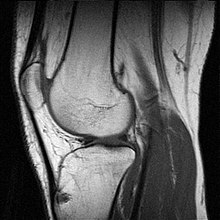

Bildgalerie

-

MRT des Sprunggelenks in T1-Wichtung -